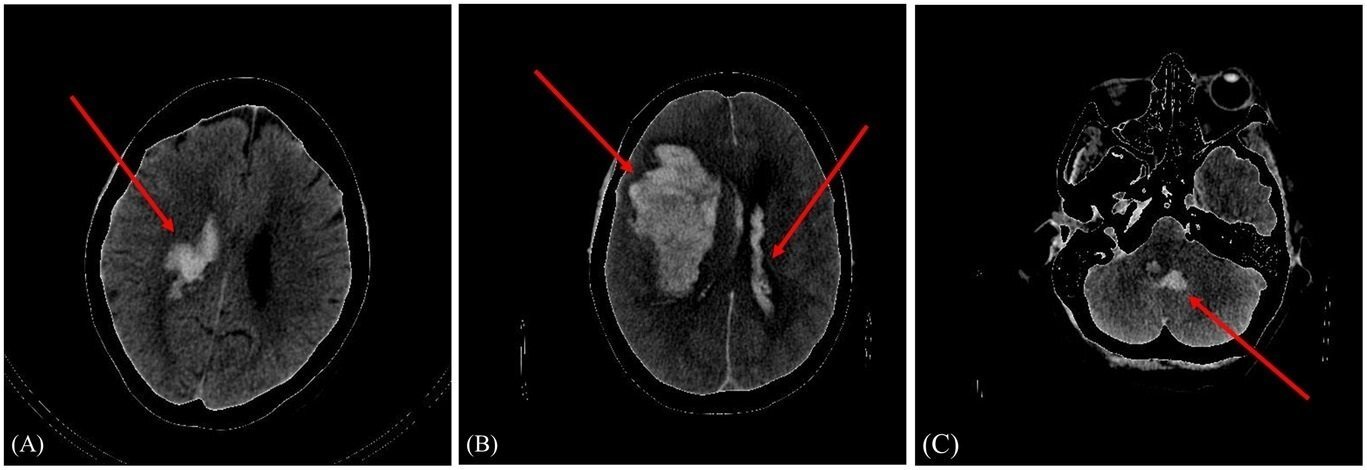

Investigadores del Instituto de Física de Cantabria (IFCA) han participado en la creación de un modelo capaz de predecir el pronóstico, favorable o no, de un paciente tras sufrir una hemorragia intracraneal.

Hasta ahora existían varios modelos de predicción para la detección de la hemorragia cerebral. Lo novedoso en este caso es que se presenta un modelo de aprendizaje profundo que predice el pronóstico de la enfermedad, es decir, si el paciente evolucionará favorablemente o no.

"Incluimos en el estudio a 262 pacientes de Cantabria que llegaban al servicio de urgencias de Valdecilla con sospechas de hemorragia intracraneal y con las imágenes de los distintos TAC cerebrales y sus datos clínicos, entrenamos un modelo personalizado para poder clasificar a los pacientes en mal pronóstico y buen pronóstico, utilizando un modelo híbrido", ha explicado Amaia Pérez.

El modelo se conoce como híbrido porque incluye dos grupos de datos: las imágenes del TAC y datos de cada paciente, y, por tanto, el rendimiento de la red mejora, "a más datos, mejores predicciones". Esos datos se obtienen de información personal, como la edad, sexo, si el paciente es fumador o consumidor de alcohol habitual o si tiene antecedentes médicos, entre otros.